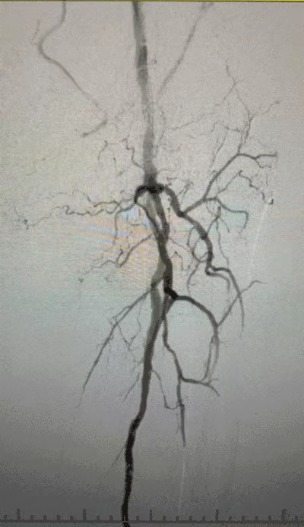

· Imaging preoperatorio: stenosi calcificata grave e diffusa nelle arterie degli arti inferiori bilaterali

Data la complessa condizione vascolare, abbiamo selezionato il sistema di catetere di dilatazione del palloncino IVL periferico ThorCrack. A causa della tolleranza limitata del paziente, sono state eseguite procedure interventistiche in scena su entrambi gli arti inferiori.

Dopo la procedura, la stenosi arteriosa è migliorata in modo significativo, il flusso sanguigno è aumentato e la temperatura della pelle è aumentata. Non si sono verificate complicanze postoperatorie. Sia il paziente che il team chirurgico sono stati molto soddisfatti dei risultati.